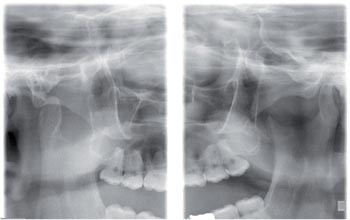

Dislocated Jaw X Ray Collection 2022 Dislocated Jaw X Ray Collection 2022

Dislocated Jaw X Ray

Learning Radiology - Dislocated, Mandible, Mandibular, Dislocation Dislocated Jaw: Symptoms and Treatment Bilateral temporomandibular joint dislocation | Radiology Case ... Pretreatment X-ray showing the anterior dislocation. | Download ... Learning Radiology - Dislocated, Mandible, Mandibular, Dislocation Dislocated Jaw X Ray